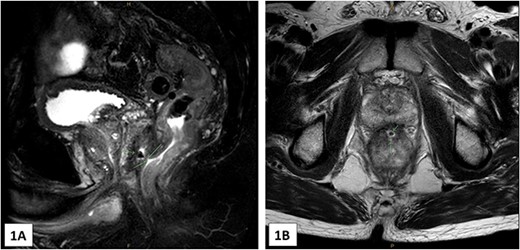

Radiotherapy was commenced 3 weeks following the spacer insertion, with a dose plan of 60 Gy divided into 20 fractions. Prior to commencing the 12th fraction, it was noted that the SpaceOAR Vue had disappeared. The patient had also noticed passing a gel-like substance per rectum in the days preceding this discovery. There had also been a single episode of small-volume rectal bleeding. Radiotherapy was ceased, and an MRI pelvis was completed, which showed a 3 mm sinus between the recto-prostatic angle and the low rectum (Fig. 1A and B). In addition, there was a small collection at the recto-prostatic angle, which was accompanied by significant granulation and fibrous tissue.

(A) and (B)—MRI images (A in sagittal, B in axial) showing the 3 mm tract from the low rectum extending into the recto-prostatic angle. This is in connection with a small collection at the recto-prostatic angle.